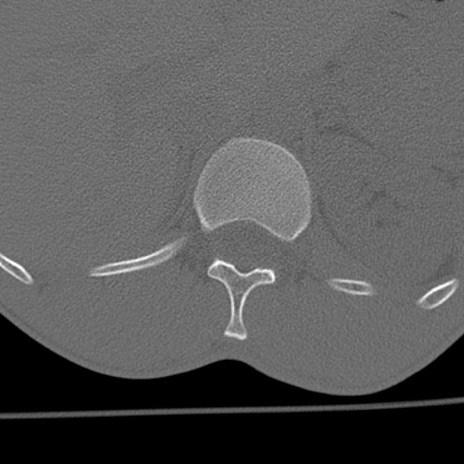

症例3 腰椎CT(横断像)

腰椎CT